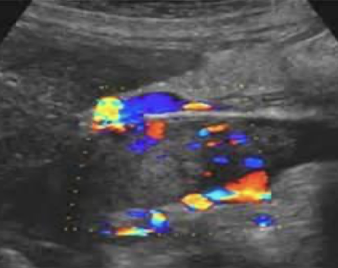

pseudoaneurysm

not lined by all 3 AO layers; blood is escaping from hole in intima layer —> outpouch and pseudo (“fake”) aneurysm

pseudoaneurysm with color Doppler

color appearance of “yin-yang” sign in sac (indicates pseudoaneurysm)

pseudoaneurysm with PW Doppler

classic “to-and-fro” Doppler signal obtained in neck of pseudoaneurysm

above baseline (positive)=blood going TO structure

below baseline (negative)=blood going AWAY from structure